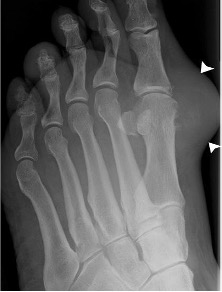

Rheumatoid arthritis

- Typically involves metatarso-phalangeal joints in a bilateral symmetrical fashion

- Early findings are soft tissue swelling, joint effusions and periarticular osteoporosis

- Progressive joint space narrowing and periarticular erosions as synovial pannus invades cartilage and bone

- Generalised osteoporosis and characteristic valgus deformities of the toes progressing to gross subluxation and dislocation in severe cases

- Midtarsal and hindfoot involvement is present in long-standing cases

Rheumatoid arthritis with symmetrical MTP joint loss, erosions and subluxation